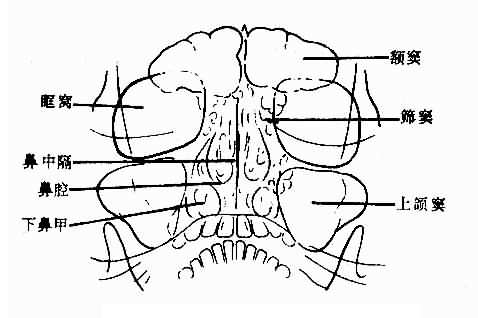

平片是检查鼻窦的基本方法。一般取坐位,鼻窦显示较好,且可查出鼻窦内积液。常用枕颏位,可显示两侧额窦筛窦上颌窦及鼻腔。正常所见,见图5-2-4。

图5-2-4 正常鼻窦(枕颏位)

额窦:多呈扇形,腔内可有骨性间隔。窦腔透明度因骨壁各部厚薄不同而不均。大小及形状个体差别较大,两侧多不对称。一侧或两侧可不发育或发育不良。

筛窦:呈蜂窝状居鼻中隔两侧和眼眶之间,其外壁为眼眶内壁。枕颏位上,蜂窝上部为前组窦,蜂窝下部为后组筛窦。蜂窝小房透明,间隔清晰、锐利,两侧多较对称。

上颌窦:居眶下方,鼻腔外侧,呈尖向下的三角形。上颌窦较透明。如嘴唇较厚,与下部重迭,可使窦腔下部密度较大,鼻翼较大,可从内壁上中部向窦腔内突入呈半圆形软组织重迭影,两侧对称,不难确认。岩骨可投影于窦腔下部,使窦腔下部密度高,不可误认为液面。两侧上颌窦的大小、形状和透明度多对称,有时一侧较小,透明度较低。

蝶窦:用颏顶位观察。呈近似椭圆形透明影,窦腔清晰、锐利。大小及外形个体差别较大,两侧可不对称。

鼻腔:鼻腔透明,鼻中隔为纵行致密带影,近于中线,多稍向一侧弯曲,上鼻甲不易显示,中鼻甲骨片垂直,下鼻甲骨片卷曲。鼻甲粘膜厚,由气体衬出。鼻甲大小个体差别较大,两侧可不对称。